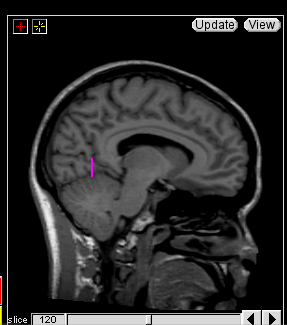

Trace the Central Sulcus in the sagittal view. Select a medial sagittal slice where the “dots” from the sulci lines drawn in the axial view are visible. Trace this sulcus inferiorly to the corpus collosum (Fig 7-8).

Figure 7                  Figure

8